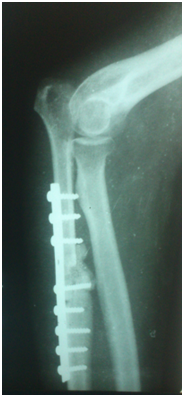

Under general anaesthesia tumour was exposed through posterior approach to elbow (Figure 3). Proximal ulna with tumour and 2cm of normal bone was excised (Figure 4). Another team of surgeons harvested required length of free fibular graft from upper fibula from ipsilateral leg. Head of the fibula was shaped to match the olecranon process of ulna and tensor fascia lata was covered over fibular head to act as articular surface (Figure 5). Graft was fixed to ulna using semi tubular plate and a K-wire was put for temporary immobilisation of elbow in 90degree flexion. Triceps tendon was sutured to the graft at proximal end. Specimen was sent for histopathological examination which confirmed the diagnosis of Osteoclastoma (Figure 6). Immediate post op X ray confirmed the proper fixation.

Post op period was uneventful. K wire was removed after 3 weeks and mobilisation of elbow was started. Patient was regularly followed up for 2 years for radiological union of the graft, functional outcome of the elbow and for possible recurrence or metastasis to lungs. Radiological union of the graft was seen as early as 4 months. At the end of 2 years patient is pain free and has a stable and functional elbow (Figure 7). No recurrence or metastasis of tumour seen. Donor site is also pain free and patient is walking comfortably.

Figure 7 Follow up X-ray after 2 years.